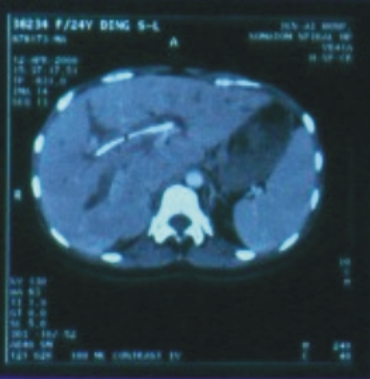

| 24歲/女性

(肝癌) |

| 89/3/3(治療前) |

89/4/12(治療後) |

| 腫瘤大小:5x5x4公分

|

完全消失 |